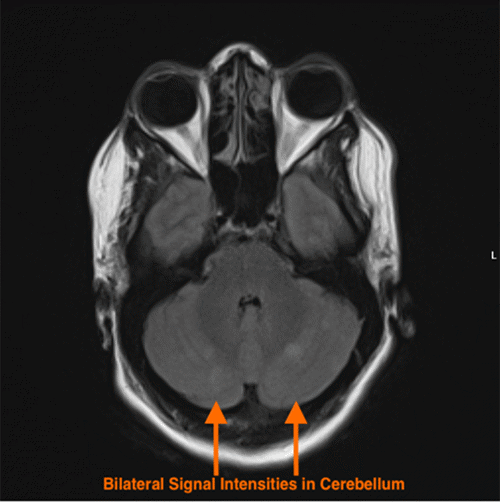

The secondary survey was notable for abrasions to the forehead and anterior chest, in addition to a fractured left fifth digit. A chest radiograph was unremarkable. Radiographs of the lower extremities confirmed bilateral displaced femoral shaft fractures (Figure 1). Bilateral Hare traction was applied, and the patient proceeded to a trauma pan-computed tomography (CT) scan. CT imaging of the head, cervical spine, and chest showed no acute traumatic abnormalities. However, the CT scan of the abdomen and pelvis incidentally revealed real-time fat emboli (density approximately -100 Hounsfield units) in transit within the bilateral femoral veins (Figure 2); this study was otherwise negative for acute intra-abdominal or pelvic trauma.

Figure 1. Bilateral Displaced Femoral Shaft Fractures at Presentation. Published with Permission

Anteroposterior radiograph of the bilateral femurs obtained upon initial presentation, demonstrating acute, displaced fractures of the femoral shafts